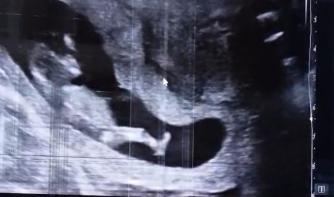

Afgelopen weekend een foto shoot gehad met kinderen aanhang en kleinkinderen helaas was het erg fris en hadden niet alle kinderen er zin in. Maar mijn dochter Lisa had een verrassing voor haar drie broers ZE IS ZWANGER eindelijk na 4 jaar wachten en ziekenhuis. Kleinkind nummer 6 is onderweg , nog meer reden om te vechten tegen deze kutziekte.  Ik mag het eindelijk van de daken schreeuwen heb 10 weken mijn mond moeten houden.🩷🩵 Nog even afwachten tot de foto’s klaar zijn. De pijn in mijn keel begint steeds erger te worden , er zit ook vocht in mijn gezicht links niezen of hoesten is echt een hel . 4 x per dag paracetamol haalt nog een beetje de scherpe randjes eraf. Vanochtend was het weer vroeg dag 8.25 moest ik er zijn dus 7.40 de deur uit ,anders staan we vast en komen te laat. Linac B was kapot dus we moesten naar E . Nieuwe mensen die mij hielpen. Het masker zat strak door het vocht in mijn gezicht . Wat duren die minuten dan lang zeg.